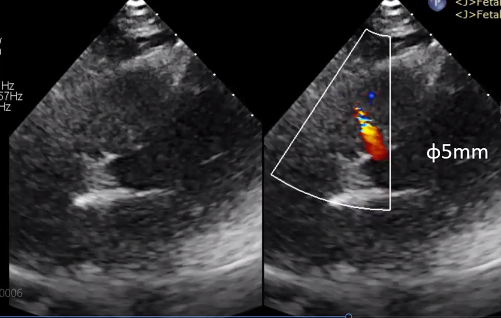

经检查诊断为膜部VSD,术前超声测量VSD缺损直径为5mm,轻度左心室容量超负荷,左心室舒张末期内径51mm。

(图:术前超声)